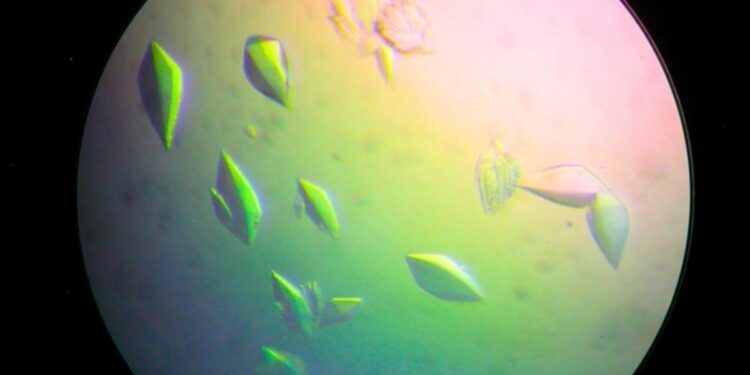

Los científicos han descubierto una proteína que puede detener directamente el daño del ADN y hasta reparar el código genético que ya ha sido dañado. Además, teóricamente es capaz de insertarse en cualquier organismo, por lo cual podría facilitar el desarrollo de una vacuna contra el cáncer, entre muchas otras aplicaciones.